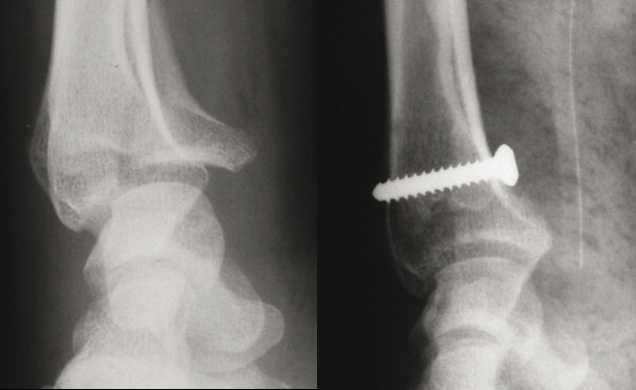

© Guillaume Herzberg, La Revue du Praticien (À gauche) Fracture articulaire parcellaire marginale antérieure. (À droite) Traitement : ostéosynthèse à foyer ouvert par vissage ou plaque vissée.